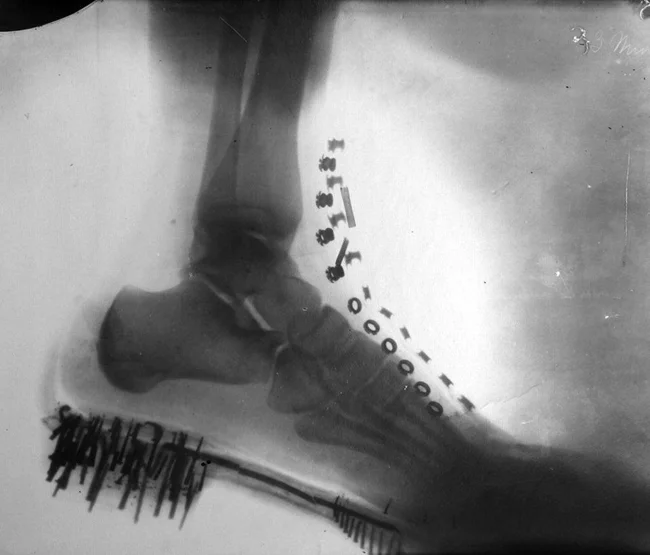

1. Рентген ноги Николы Теслы, который он сделал сам